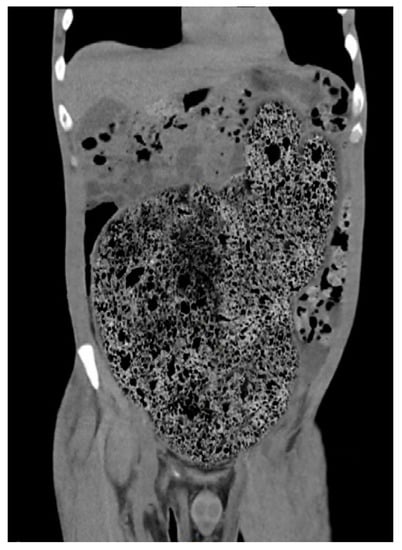

4. Diagnostic Criteria for the Acquired Megacolon

5. Complications